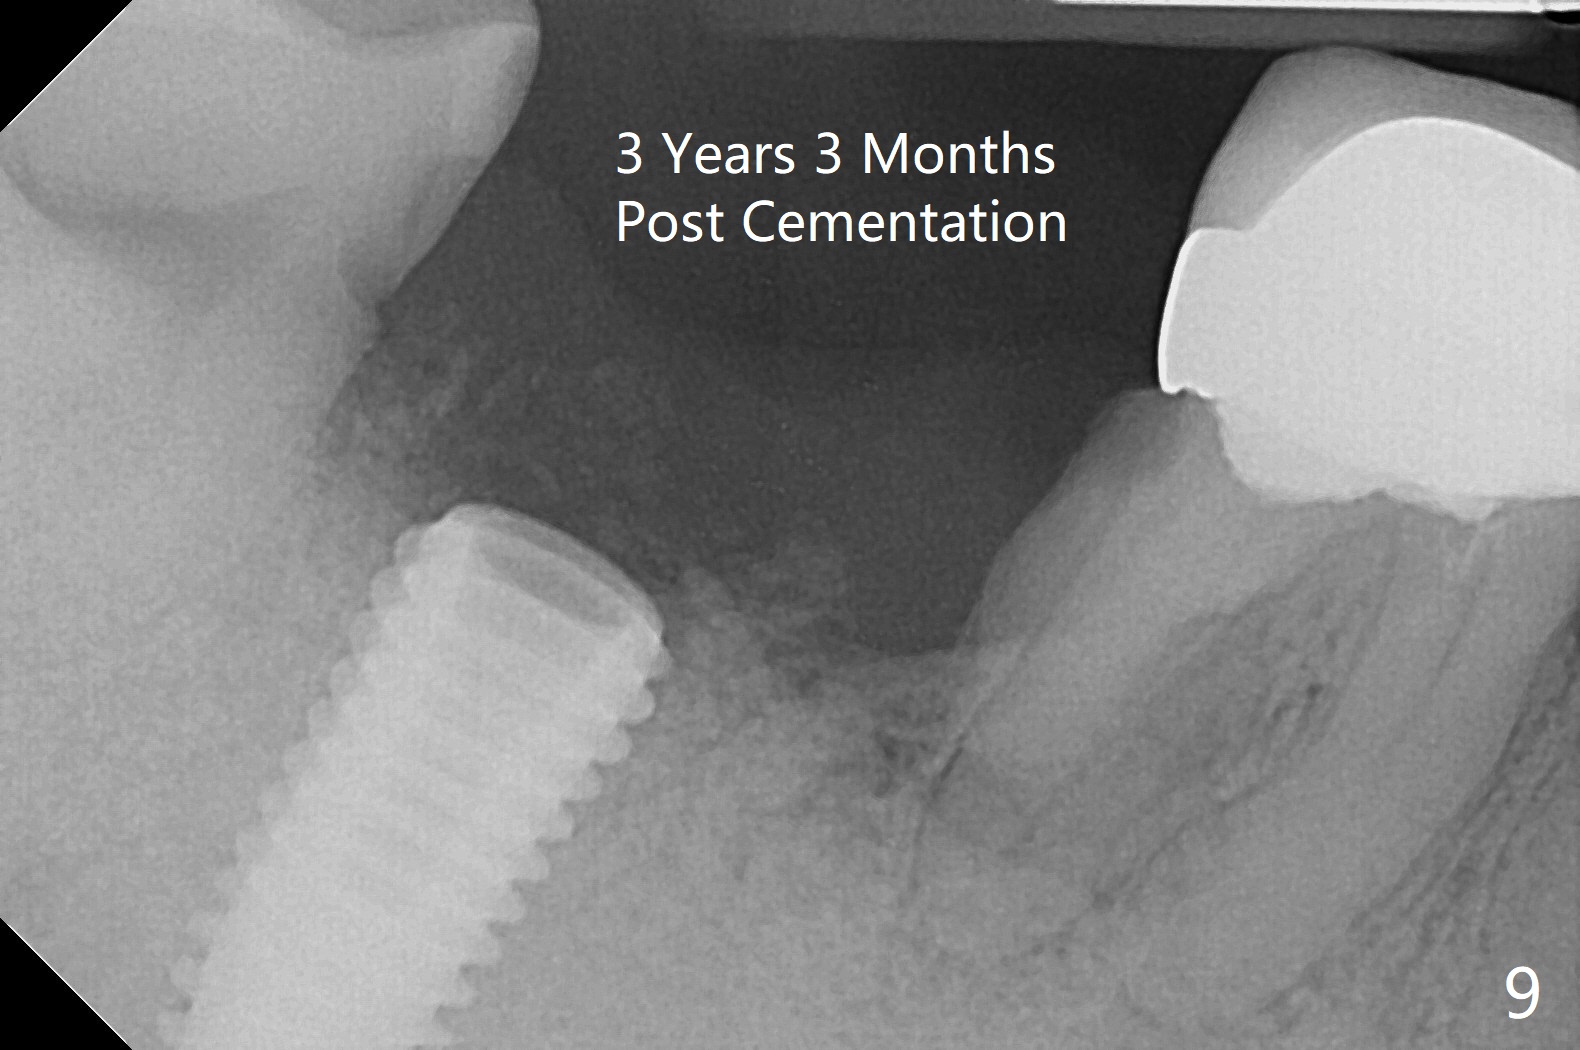

Although the tooth #30 has distobuccal root exposure (Fig.1 <), it is asymptomatic.  In contrast the tooth #31 with the distoocclusal caries (*) is symptomatic.  After use of 2 mm drill for 18 mm (lingual gingival margin), a calculated parallel pin is inserted (Fig.2 (D: 2 distal roots of the tooth #30)).  It appears that a 11.5 mm long implant is appropriate for the site; a 5 mm cuff is expected.  Following 4.8 mm drill, a 5.5x11.5 mm implant is placed initially (Fig.3) with an apical space (*) and clearance from the Inferior Alveolar Canal (red dashed line).  The implant is placed deeper with placement of a 6.5x4(5) mm abutment and bone graft (*, Fig.4,5).  After placement of collagen membrane over the graft, an immediate provisional is fabricated (Fig.6 P) with clearance from the opposing tooth (Fig.7 *).  There is no bone loss 3.5 months postop (Fig.8).  In fact the abutment has not been seated completely since its placement (Fig.4,5,8).  The crown/abutment dislodges 3 years 3 months post cementation (Fig.9).  The latter occurs for long incubation time because of opposing partial denture (Fig.10).  After trimming proximal surfaces (Fig.11: arrowheads), the abutment remains incompletely seated (Fig.11) due to possible crestal bone interference (Fig.11 *).  The smaller abutment by itself remains unseated (Fgi.12).  One size small one is completely seated (Fig.13).  Impression is taken.  Two weeks later the abutment margin is supragingival.  After screw torque at 20 Ncm, the crown is cemented with access hole.  Excess cement is removed.